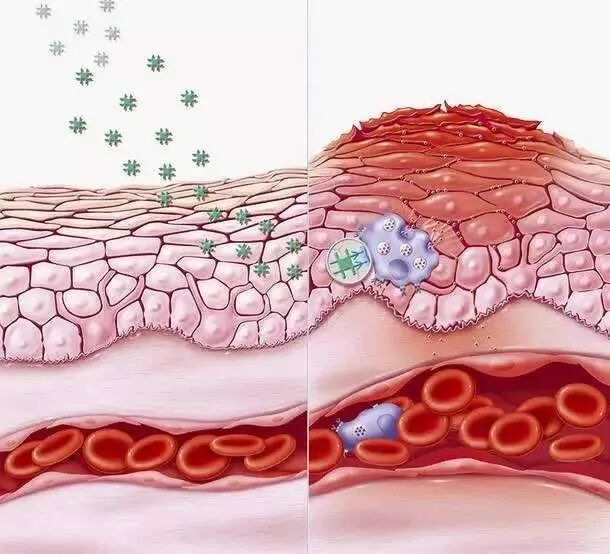

炎症是人体免疫系统的自然反应,是身体自我保护的一种表现。当机体受到损伤或病原体入侵时,免疫系统会立即动员起来,引发炎症反应,以清除有害物质并修复受损组织。

急性炎症是机体对突然损伤(如创伤、感染)的即时反应,通常表现为红、肿、热、痛和功能障碍,持续时间较短,随着损伤修复而消退。